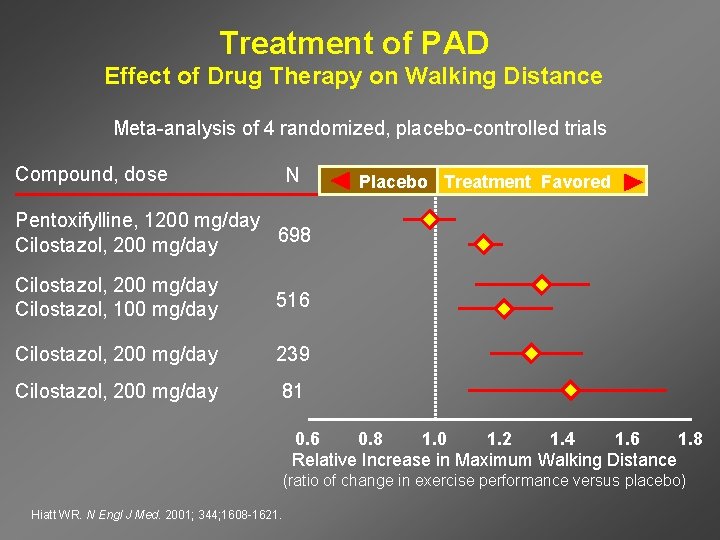

Treatment of PAD Effect of Drug Therapy on Walking Distance Meta-analysis of 4 randomized, placebo-controlled trials Compound, dose N Placebo Treatment Favored Pentoxifylline, 1200 mg/day 698 Cilostazol, 200 mg/day Cilostazol, 100 mg/day 516 Cilostazol, 200 mg/day 239 Cilostazol, 200 mg/day 81 0. 6 0. 8 1. 0 1. 2 1. 4 1. 6 1. 8 Relative Increase in Maximum Walking Distance (ratio of change in exercise performance versus placebo) Hiatt WR. N Engl J Med. 2001; 344; 1608 -1621.